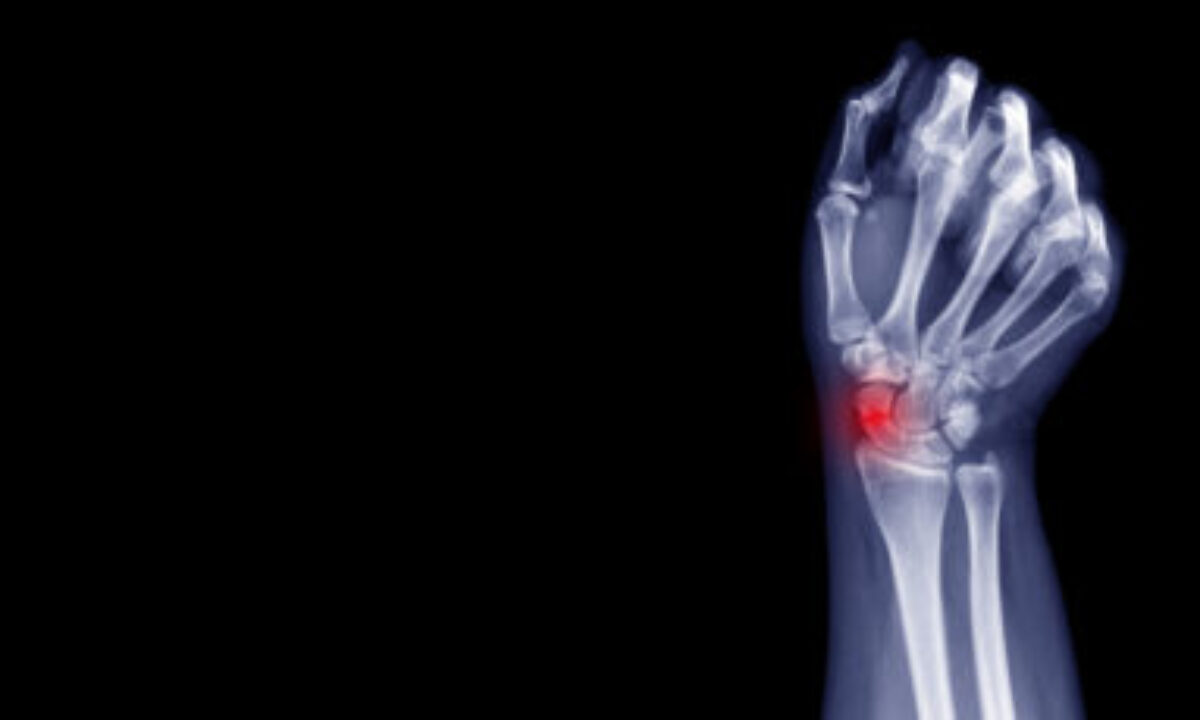

Arm Hairline Fracture . Depending on the severity of the fracture, the. One of the most common causes. What you need to know. Forearm fractures are generally the result of trauma to the radius or ulna, the two bones that make up the forearm. The forearm is made up of two bones, the ulna and the radius. Are forearm fractures something i can treat at home? Pain, tenderness, and swelling are the most recognizable signs of a fracture to the arm. A humerus fracture is the medical name for breaking the bone in your upper arm (your humerus). A broken arm involves one or more of the three bones in your arm — the ulna, radius and humerus.